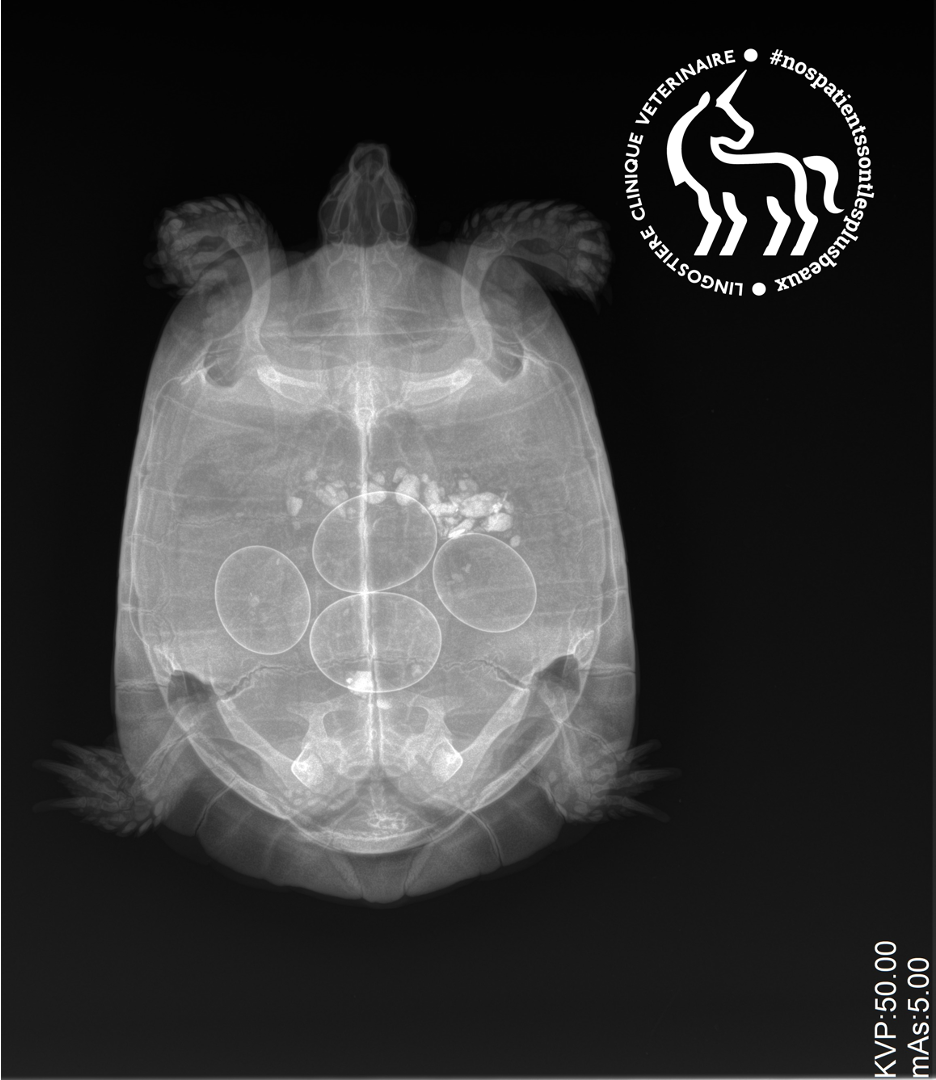

Rétention d’œufs

Identifier la dystocie, les risques de péritonite et les solutions chirurgicales.

Stase folliculaire

Troubles de l’ovulation pré-ovulatoire : diagnostic échographique et chirurgie.